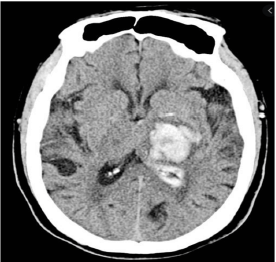

Paciente de 66 anos do sexo feminino com antecedente de hipertensão, AVC hemorrágico há 2 anos sem sequelas, e arritmia, sem seguimento médico adequado, fazendo uso irregular de captopril. Além disso, apresentou traumatismo craniano leve na semana passada, sem maiores repercussões.

Procura pronto-socorro com queixa de déficit neurológico agudo, com aparecimento há 40 minutos. À admissão, exibe PA 150x92, FC 77, FR 18, SatO2 96% a.a., glicemia capilar de 90mg/dL. Ao exame neurológico, apresenta hemiplegia à direita, afasia global e paralisia facial de padrão central, com NIHSS = 15. Realizada TC de crânio, abaixo:

Neste momento, a conduta mais adequada para essa paciente seria